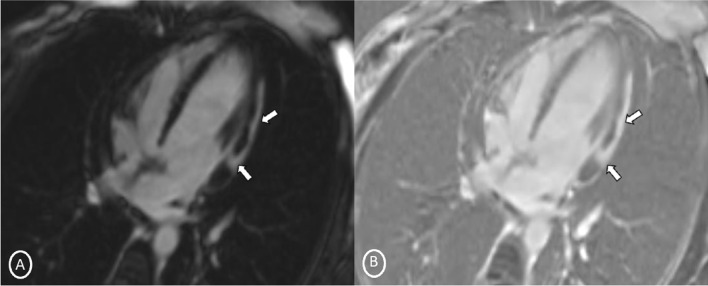

A 19-year-old female had presented to our Emergency Department, complaining of sudden severe chest and epigastric pain since 1 day, which was associated with sweating. The pain was radiating to neck and left arm. The pain did not relieve on rest but subsided on medications. Similar episodes were also reported in the past few days, however, with less severity. The patient confirmed to not having shortness of breath, palpitation, syncope, dizziness, nausea, emesis, fever, or cough. There was no history of any previous cardiac ailment/surgery/other identifiable cardiovascular risk factors or any other history of infection. There is no evidence to suggest chest wall trauma. There is no history of comorbidities or any history of smoking. There is no significant family history or any similar past history. Upon admission, patient was conscious, alert with heart rate of 86 bpm, blood pressure measuring 110/60 mm Hg, 97% oxygen saturation at room air, temperature of 36.4 °C, and respiration rate of 15 breaths/min. The cardiac biomarker troponin T levels were extremely raised, measuring 50,000 pg/ml, and CK-MB was raised, measuring 111U/Lt. Laboratory findings showed that inflammation markers were normal, C-reactive protein (5.8.0 mg/L) and D-dimer (94 ng/mL). Other laboratory findings such as lipid profile, complete blood count, electrolytes, fasting blood glucose, HBA1c, and renal and liver function tests were normal. Cardiac auscultation showed normal S1, S2 without murmurs or pericardial rub and any sign of heart failure. Initial ECG revealed ST segment elevation in the leads I, aVL, V4, V5, and V6 leads, normal sinus rhythm (60 beats per min) without any other abnormalities (Fig. 1), which was resolved by day 3. Arrhythmias were not found during continuous cardiac monitoring. Echocardiogram showcased an ejection fraction of the left ventricle to be 60%, whereas the echocardiographic metrics were not very significant. Patient was then treated as ACS with a salicylate-based nonsteroidal anti-inflammatory drug (NSAID), anticoagulants, and anti-thrombolytics. CMR was done on 3 T MRI machine with acquisition including T2/STIR Dark blood four-chamber long axis; CINE images in short axis, long axis, RVOT, and LVOT; and early dynamic gadolinium enhancement images and delayed gadolinium enhancement in PSIR images. T2/STIR Dark blood sequences showed T2 hyperintensity in the subepicardial region along left lateral wall (Fig. 2A, B). There was associated mild global hypokinesia with mildly reduced ejection fraction/systolic function (Fig. 3A, B). Patchy delayed gadolinium enhancement of intramural, subepicardial as all tans-mural enhancement with non-involvement of the subendocardium (suggesting a non-ischemic pattern) in multiple segments of cardiac basal (Fig. 4A, B), mid cavity (Fig. 5A, B), and apical cavity—with predominant involvement of lateral (Fig. 6A, B) and inferior wall segments in the basal cavity. There were no signs of infarction of myocardium; therefore, the patient was diagnosed with acute myocarditis (based on Lake Louise Criteria for Acute Myocarditis). Further, viral and autoimmune workups results were found to be negative. It included hepatitis (B, C), human immunodeficiency virus, Coxsackie virus, COVID-19, cytomegalovirus, Epstein–Barr virus (EBV), and Parvovirus B-19. On further analysis and detailed relevant history workup, the patient admitted to using cannabis for the past 1 year with last exposure being 3 days before admission. On the basis of detailed clinical history, findings on CMR with other negative viral markers, and possible etiological factors, a final diagnosis of myocarditis presumed secondary to marijuana/cannabis toxin abuse was made. Patient was released from the hospital on the seventh day with advised conservative treatment. The patient was counseled to abstain completely from cannabis or related drugs. Patient was advised to repeat a CMR control, three months later. A 3–4-month restriction on high-intensity activity was also given to the patient following discharge.